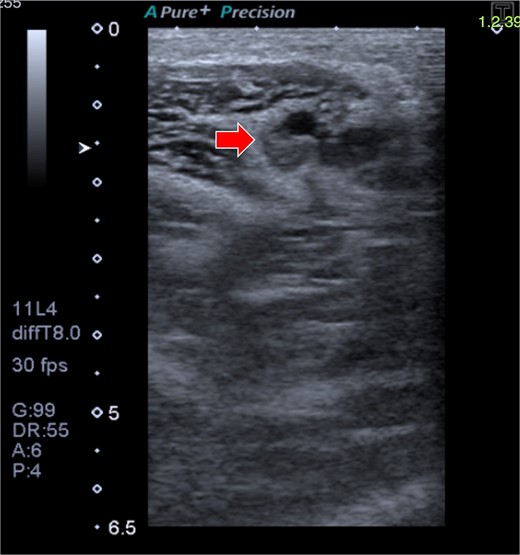

A 33-year-old woman with a history of oral contraceptive use and a BMI of 23.4 kg/m2 presented with breast hypoplasia. She was preoperatively evaluated and received an ASA I. A prepectoral augmentation mammoplasty was performed under general anesthesia. Même® MesmoMS® (Polytech Health & Aesthetics, Dieburg, Germany) 300-ml round implants were placed. The operative time was 80 minutes, and graduated compression stockings were used. On postoperative Day 7, the patient presented with pain, swelling, and erythema over the medial aspect of the right elbow and arm, with vital signs remaining normal. Doppler ultrasound revealed a right UEDVT (Fig. 2), and tomography showed thrombosis in the axillary and humeral veins (Fig. 3).

Doppler ultrasound shows DVT in the right axillary vein (arrow).